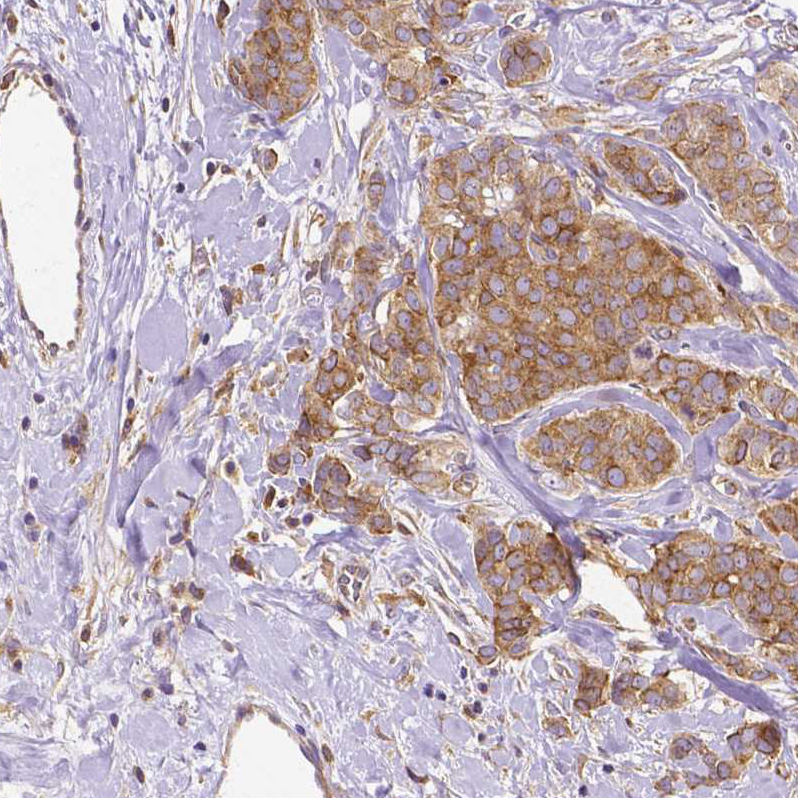

Immunohistochemical staining of human testis shows moderate to strong cytoplasmic positivity in a subset of cells in seminiferous ducts.